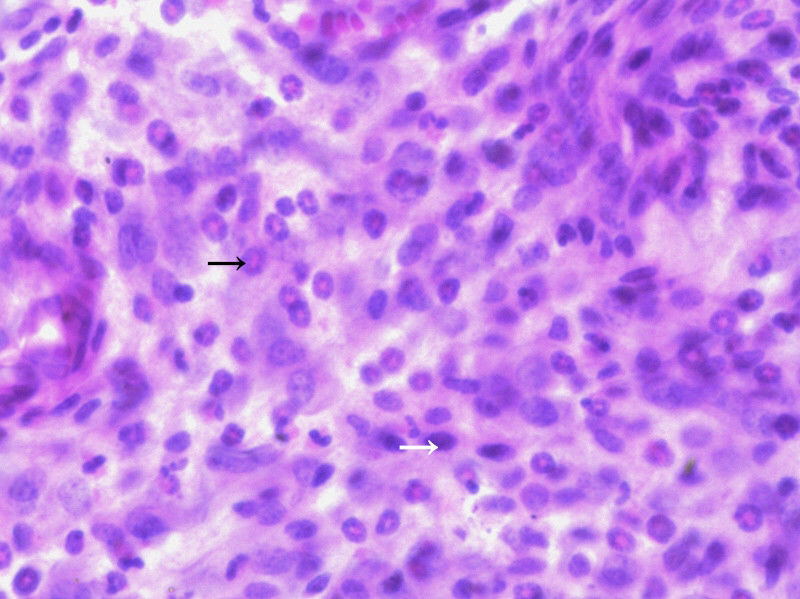

请问,箭头指向的细胞是什么细胞? 发自小木虫IOS客户端 |